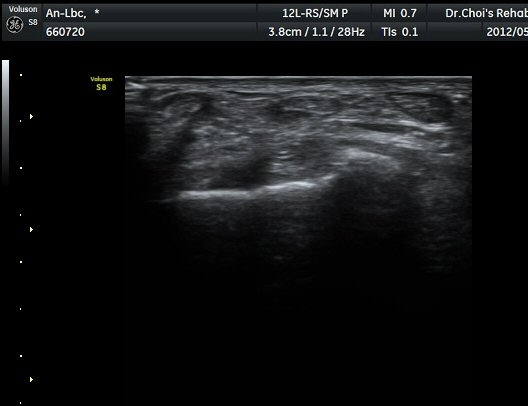

¶Ñ·ÈÇÏ´Ù. Àü°æ°Ç Á¾´Ü¸é°Ë»ç¿¡¼­ °ÇÀÇ ºÎÁ¾°ú °Ç ÁÖÀ§ ¼ö¾× Àú·ù°¡ °üÂûµÈ´Ù(»çÁø 3). °ÇÀÇ

ºÎÁ¾°ú ¼ö¾×Àú·ù´Â °ÇÃø°ú ºñ±³ÇÏ¸é ¶Ñ·ÈÇÏ´Ù(»çÁø 5).¤·